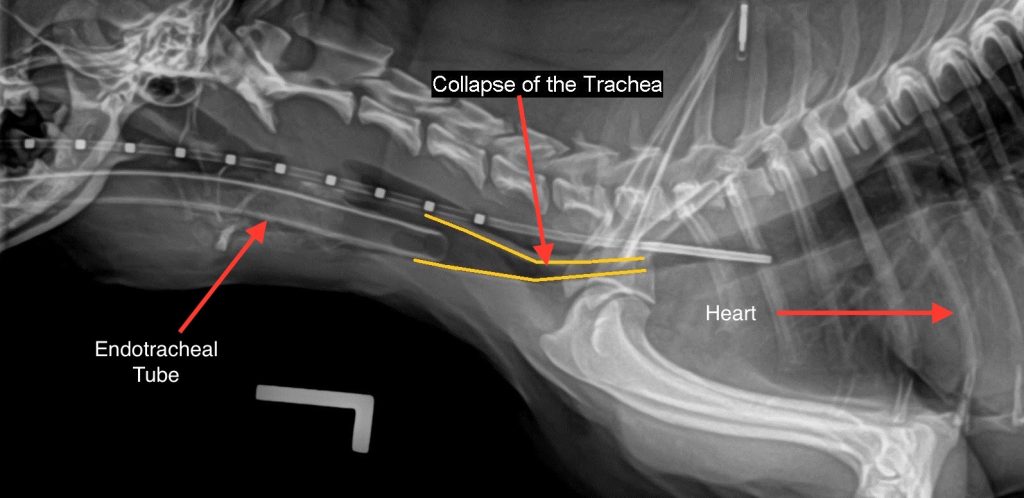

X光檢查

- 胸腔及頸部側位X光:是最基礎的影像學檢查,可初步判斷氣管是否狹窄或變形,並排除其他心肺疾病。

- 吸氣與呼氣階段的動態X光:因為氣管塌陷是動態變化,靜態X光可能會漏診,大約有44%誤判率。動態X光(螢光透視)能清楚顯示氣管塌陷的位置及程度,準確度更高。

臨床檢查:狗狗明顯喘不過氣,呼吸速率為每分鐘 60 下,伴隨明顯的上呼吸道喘鳴與鼾聲,並不時咳嗽。體溫為 39.9°C,心跳為每分鐘 160 下,黏膜呈現暗淡或發紺的顏色。由於懷疑是氣管塌陷,我們安排了胸部X光檢查。

胸部X光檢查:小米的頸部與胸前段氣管有明顯狹窄現象,與氣管塌陷的典型影像相符。綜合牠的臨床症狀與影像結果,我們診斷小米為氣管塌陷(第三級到第四級)。